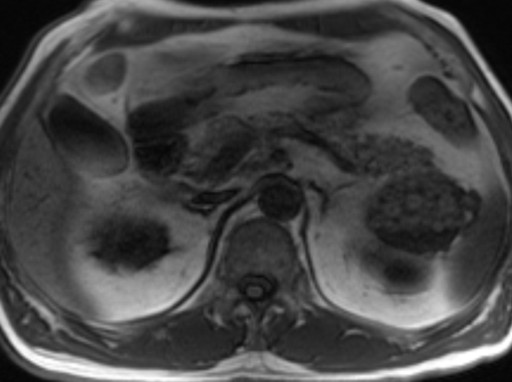

A 63-year-old man with a previous history of colon cancer, resected 3 years earlier, presented for a routine clinical follow-up. Physical examination and past medical history were unremarkable, except for an appendectomy at the age of 15. The patient had had a history of intermittent and mild left upper quadrant abdominal pain not associated with meals before a resection for colonic cancer; CA 19-9, CEA and amylase were unremarkable. There was no body weight loss or fever, and the patient had no previous history of pancreatitis. An abdominal ultrasound was performed which showed a 7 cm non homogeneous anechoic mass at the level of the pancreatic tail. An MR scan was subsequently obtained which confirmed the presence of a 7x4 cm lesion at the level of the pancreatic tail, close to the splenic hylum. This lesion showed a complex structure with multiple sub-centimeter nodules within it. In particular, the lesion was homogeneously hypointense on the pre-contrast T1-weighted MR images (Figure 1), showing a mild rim of enhancement after intravenous contrast administration while maintaining the hypointensity of the central core constant (Figure 2); on T2-weighted MR images, the pancreatic mass had a "cheerios-like" appearance, showing multiple small nodules with a central hypointensity and peripheral hyperintensity; a fluid-level was also present at the bottom of the lesion (Figures 3 and 4), most likely reflecting the inflammatory changes of the lesion. The patient subsequently underwent a distal pancreatectomy and splenectomy (due to the proximity of the lesion to the splenic hylum). Histological examination demonstrated the benign nature of the lesion consisting of a pancreatic lymphoepithelial cyst. The surface of the cyst was smooth, the lesion was filled with keratinous material and the walls were lined with stratified squamous epithelium which was surrounded by a layer of lymphoid tissue composed of small lymphocytes, plasma cells and germinal centers, without signs of atypia (Figure 5). The periphery was composed of normal pancreatic tissue. The postoperative course was uneventful and the patient was discharged from the hospital 10 days after the surgical intervention.

Figure 1. Pre-contrast axial-T1-weighted MR image showing a hypointense mass of 7x4 cm in the pancreatic tail, close to the splenic hylum. |